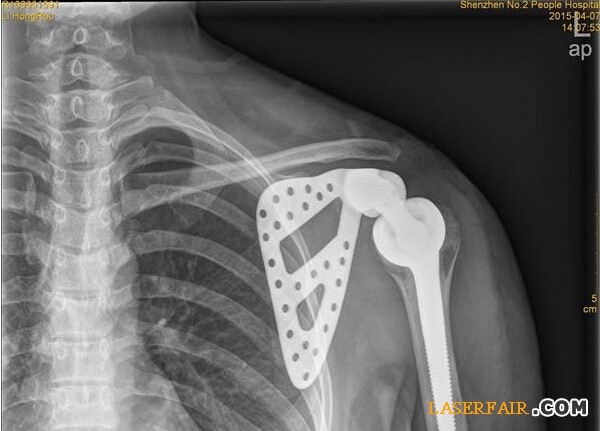

近日,深圳市第二人民醫(yī)院收治了一位27歲女患者,該患者肩胛部位的骨頭已經(jīng)被腫瘤侵蝕四分之三,亟需手術(shù)切除。但是如果貿(mào)然切掉整個(gè)肩關(guān)節(jié),不僅手術(shù)風(fēng)險(xiǎn)大,恢復(fù)后病人生活也難以自理。于是該院利用3D打印技術(shù)制備出與患者肩胛骨完全匹配的鈦合金假體,置換掉原來腫瘤壞死的肩胛骨,打造了一個(gè)新的“肩膀”。

隨著3D技術(shù)的日臻成熟,該醫(yī)院與3D打印公司展開治療研究,針對(duì)李女士的治療首次采用3D打印技術(shù)制備出與患者肩胛骨完全一致的鈦合金假體,并成功植入骨腫瘤患者體內(nèi)。

“首先是3D打印人工制作肩胛骨模型,把采集到的李女士左邊肩胛骨大小、形狀等數(shù)據(jù)通過3D技術(shù)打印出完全吻合的模型。”深圳市第二人民醫(yī)院骨關(guān)節(jié)、骨腫瘤科副主任醫(yī)師譚紀(jì)鋒介紹,然后根據(jù)模型設(shè)計(jì)出手術(shù)方案,在模型上標(biāo)注手術(shù)的螺釘孔、切除邊界,實(shí)現(xiàn)手術(shù)精準(zhǔn)化。”由于3D模型采用的樹脂材料不能直接植入人體內(nèi),因此醫(yī)院將模型送至人工關(guān)節(jié)制作廠,制作出鈦合金人工肩胛骨。在為李女士進(jìn)行腫瘤完整切除后,再將鈦合金人工肩胛骨植入患者體內(nèi)。由于3D打印實(shí)現(xiàn)了“量體裁衣”,因而鈦合金人工肩胛骨能實(shí)現(xiàn)精準(zhǔn)匹配。

14日,記者從醫(yī)院獲悉,李女士的手術(shù)很成功,很快就可以出院了。據(jù)了解,這是深圳乃至華南地區(qū)首例肩胛骨3D打印鈦合金假體植入術(shù)。